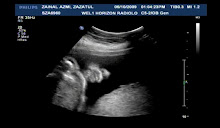

menghitung hari...